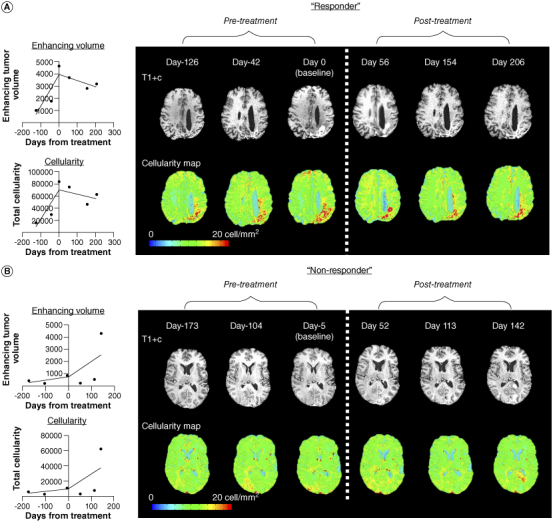

Aim: A radio-pathomic machine learning (ML) model has been developed to estimate tumor cell density, cytoplasm density (Cyt) and extracellular fluid density (ECF) from multimodal MR images and autopsy pathology. In this multicenter study, we implemented this model to test its ability to predict survival in patients with recurrent glioblastoma (rGBM) treated with chemotherapy.Methods: Pre- and post-contrast T1-weighted, FLAIR and ADC images were used to generate radio-pathomic maps for 51 patients with longitudinal pre- and post-treatment scans. Univariate and multivariate Cox regression analyses were used to test the influence of contrast-enhancing tumor volume, total cellularity, mean Cyt and mean ECF at baseline, immediately post-treatment and the pre- and post-treatment rate of change in volume and cellularity on overall survival (OS).Results: Smaller Cyt and larger ECF after treatment were significant predictors of OS, independent of tumor volume and other clinical prognostic factors (HR = 3.23 × 10-6, p < 0.001 and HR = 2.39 × 105, p < 0.001, respectively). Both post-treatment volumetric growth rate and the rate of change in cellularity were significantly correlated with OS (HR = 1.17, p = 0.003 and HR = 1.14, p = 0.01, respectively).Conclusion: Changes in histological characteristics estimated from a radio-pathomic ML model are a promising tool for evaluating treatment response and predicting outcome in rGBM.